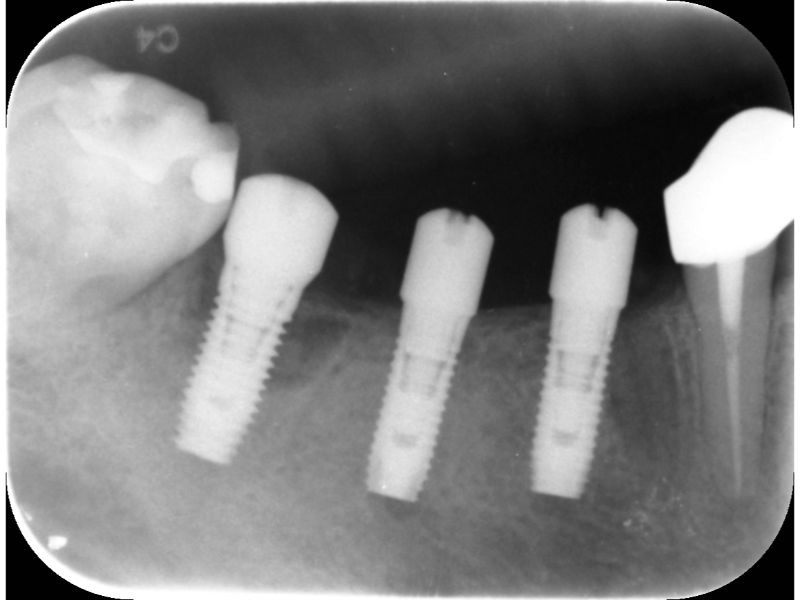

案例一